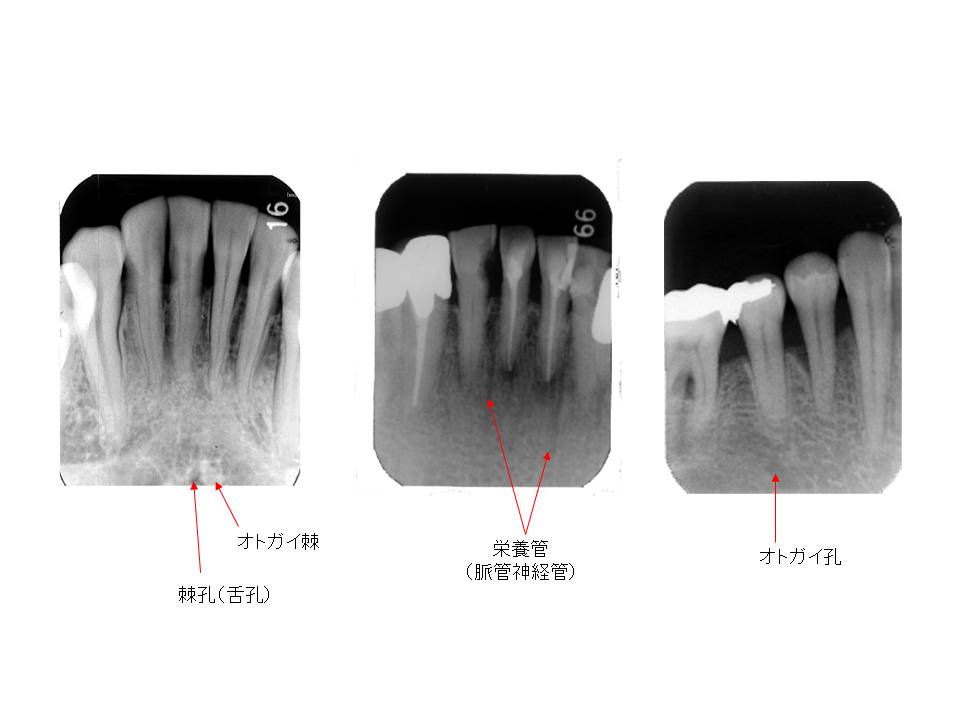

口内法(二等分法・咬合法)撮影の解剖